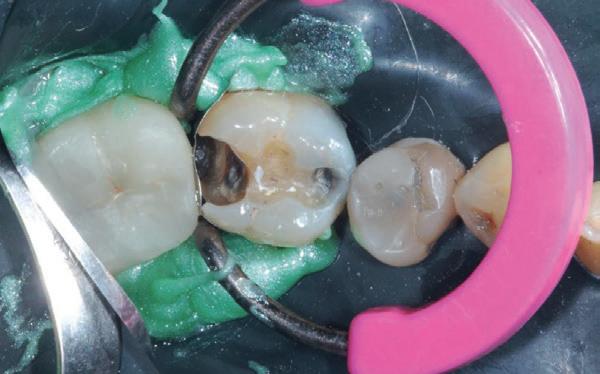

Voordat je aan een wortelkanaalbehandeling begint, zorg je voor (of maak je) een goede beginfoto waar het te behandelen gebitselement volledig op staat afgebeeld. Deze foto geeft essentiële informatie: de grootte van de pulpakamer en de ligging ervan; het aantal en de vorm van de wortels en de breedte van hun wortelkanalen en de lengte van de wortels. Hiermee kan je de DETI-score bepalen en de moeilijkheidsgraad inschatten. De grootte en de ligging van de pulpakamer op de röntgenfoto in combinatie met de ideale anatomische vorm, zoals in foto 1 is aangegeven, bepaalt de uiteindelijke vormgeving van de opening. Bij de molaren liggen de kanaalingangen in de buurt van de knobbeltoppen. Als die niet meer in originele staat

(kroon, restauratie) zijn, kan je ook de wortel gebruiken. Soms moet je net subgingivaal sonderen, maar de kanaalingang ligt in het middel van de wortel. Als je die plek visualiseert en projecteert op je opening, boor je de goede kant op. Nog een tip: wees bij het openen niet spaarzaam met het wegnemen van aanwezig restauratiemateriaal (wees wél spaarzaam met het onnodig wegnemen van tandweefsel).

De casus

De verwijzend tandarts is bezig om een wortelkanaalbehandeling uit te voeren in gebitselement 27. Er zijn vier kanalen gevonden, maar helaas breekt er in het mesiobuccale kanaal (MB 1) een WaveOne vijltje af, maat geel (foto 2). Het lukt de tandarts niet om

3. De opening is vrij klein gekozen. In rood is de ideale opening aangegeven, de tandarts had veel meer restauratiemateriaal mogen wegnemen.

7. Hierop is nog eens de correcte opening te zien. Ik heb veel van het aanwezige amalgaam weggenomen om zoveel mogelijk ruimte te krijgen. Ook is te zien hoe ik het mesiobuccale kanaal heb moeten verbreden om bij het instrument te komen. Het palatinale kanaal is niet zichtbaar op deze afbeelding.

het vijltje te verwijderen. De patiënte wordt verwezen voor het afmaken van de wortelkanaalbehandeling.

Als ik de patiënte zie, valt me op dat de opening die de tandarts gemaakt heeft, nogal klein is (foto 3). Eigenlijk is daar niet zoveel reden toe; als ik een ideale opening inteken (in rood), dan loopt een groot deel door restauratiemateriaal. Overwogen kan worden om de aanwezige mesiale box met restauratiemateriaal weg te halen als dat het zicht op de pulpakamer vergroot – ik verwijs naar de tip hierboven (wees bij het openen niet spaarzaam met het wegnemen van aanwezig restauratiemateriaal).

Het afgebroken instrument ligt vrij diep; in het onderste 1/3 deel van de wortel. Vaak laten we het afgebroken instrument in het onderste 1/3 deels zitten, omdat verwijderen lastig is en er een kans is op schade. Daarom proberen we het te passeren en wordt het afgebroken instrument onderdeel van de kanaalvulling.

Passeren lukt mij in deze casus helaas niet. Omdat het instrument in een recht deel van het kanaal ligt, waag ik een poging om het afgebroken instrumentje te verwijderen, zodat ik het kanaal kan desinfecteren en kan vullen.

Onder microscopie en met een LN boortje zoek ik het instrumentje op. Na verificatie verwijder ik het door

met een ultrasone tip (Spartan CPR 8, bruin) rondom het vijltje materiaal weg te nemen, waardoor deze als het ware uitgegraven wordt. WaveOne vijltjes zijn irritant om te verwijderen, het nikkeltitanium materiaal wil naar een oorspronkelijke vorm (een rechte vorm) terugbuigen en daarom drukt het zich steeds vast bij het verwijderen. Staal is vaak makkelijker te verwijderen. Maar het lukt me en de wortelkanaalbehandeling kan worden afgemaakt.

Het verwijderen van een afgebroken instrument kost altijd relatief veel (gezond) tandweefsel en kent veel risico op perforatie of andere schade. Daarom is het altijd belangrijk om goed te overwegen of een vijl verwijderd moet worden.

Maar beter nog is om te voorkomen dat een vijltje afbreekt door bij de opening voldoende te prepareren voor goed zicht en voor wat we noemen een ‘straight line access’. Goede voorbereiding is het halve werk.